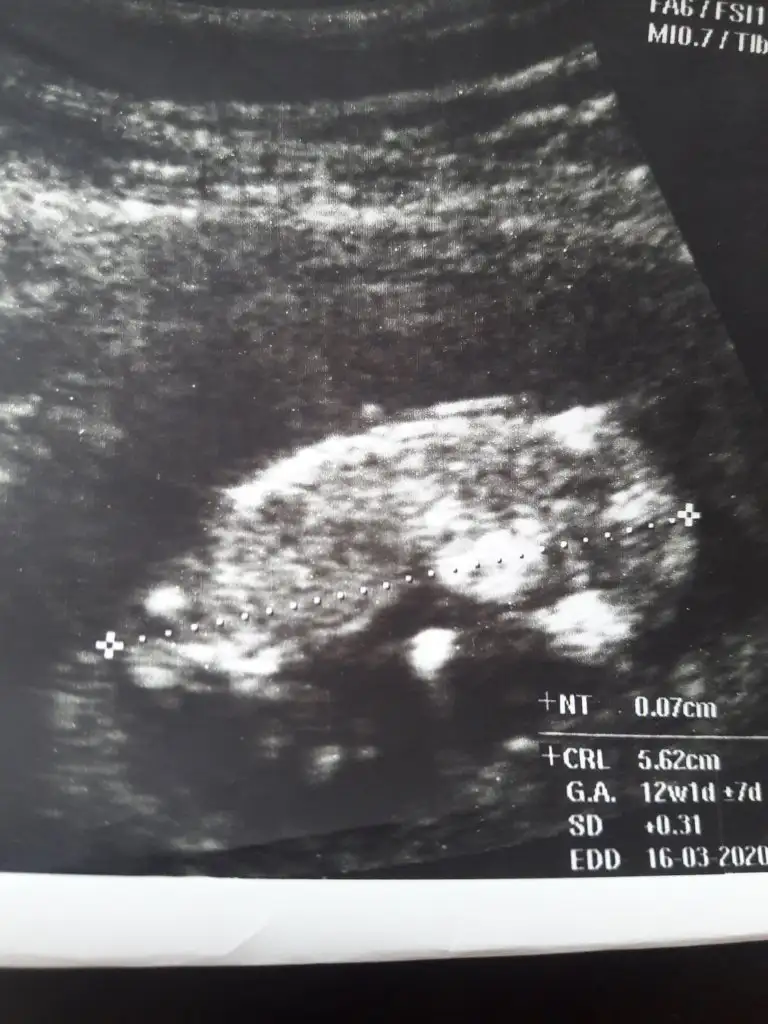

bu 12 haftalıkken

Merhaba ben de bir tahmin alabilir miyim. 11+4 haftalıkken.